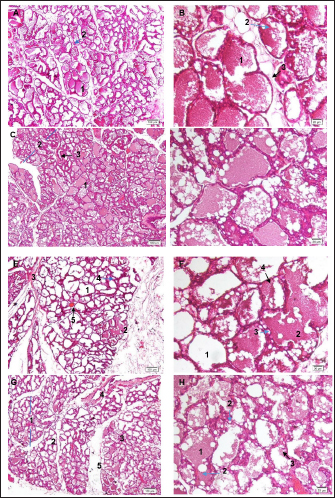

Histopathology of the mammary gland

During lactation, alveoli undergo significant changes, including increased alveolar lumen size and enhanced proliferation of epithelial cells, which indicate active milk production (Salahshoor et al., 2018; Utary et al., 2019). Histological analysis revealed that compared to the normal control group, mammary glands consisted of small lobules dispersed within adipose tissue (Fig. 2A, B), and the groups treated with blended extract had increased lobular and alveolar volume, expanded alveoli filled with breast milk, along with a reduction in adipose tissue (Fig. 2C–H). These observations indicate that the blended extracts may influence the functional aspects of alveolar development and milk synthesis.

In the 75-mg/kg group (Fig. 2D), each lobule contained a marginally larger alveolus than that in the 37.5, 150 mg/kg, and control groups, indicating a positive effect of the extract on the alveolar size. During pregnancy, glandular tissue develops into secretory alveoli surrounded by contractile myoepithelial cells. Expansion of the alveolar lumen, driven by epithelial cell growth, enhances milk production capacity.

Our results showed that lactating rats treated with the 75-mg/kg extract had notably prominent alveolar lumens, suggesting that the extract stimulated the proliferation of myoepithelial cells, leading to more alveoli and potentially higher milk production (Utary et al., 2019). In addition, the increase in lobular size and reduction in adipose tissue in treated groups indicate that the extracts promote glandular tissue expansion and optimize conditions for lactation.

Fig. 2. Effect of the blended extract of S. androgynus, M. oleifera, and C. amboinicus on mammary gland tissue. A and B control group: A) 1. alveolar-containing milk and 2. cuboidal epithelial lining cells (blue arrow) HE ×100; B) 1. alveolar-containing milk, 2. fat globules (blue arrows), and 3. cuboidal epithelial lining cells (black arrows). HE ×400; C-D Group 2 with 37.5 a blended extract: C) 1. alveolar-containing milk, 2. lobules (blue arrows), and 3. interlobular duct (black arrow) HE ×100; D) 1. alveolar-containing milk, 2. fat globules (blue arrows), 3. cuboidal epithelial lining cells (black arrows), and 4. secretory ducts. HE ×400; E and F. Group 3: 75 mg/kg of the blended extract: E) 1. alveolar, 2. alveolar containing milk, 3. connective tissues, 4. duct (blue arrow), and 5. blood vessels (black arrow) HE ×100; F) 1. alveolar, 2. alveolar containing milk, 3. fat globules (blue arrows), and 4. cuboidal epithelial lining cells (black arrows). HE ×400; G and H group 4 treated with 150 mg/kg of the blended extract: G) 1. lobules of the mammary glands (blue arrow), 2. alveolar, 3. alveolar-containing milk, 4. interlobular duct, and 5. interseptum. HE ×100; H) 1. alveolar-containing milk, 2. fat globules (blue arrows), and 3. cuboidal epithelial lining cells (black arrows). HE ×400.